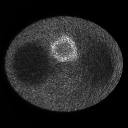

Refer to caption Refer to caption

Figure 2: Images reconstructed from the simulated data sets 1(top row) and 2(bottom row) by the classic EM algorithm(left column) and the mean images of 100 trials(right column).

In order to evaluate the qualities of the reconstructed images, we computed the mean images xsuperscript𝑥x^{\ast} from 100 noise trials as the standard images of the two data sets, respectively.

x=1100m=1100x^m,superscript𝑥1100superscriptsubscript𝑚1100superscript^𝑥𝑚\displaystyle x^{\ast}={1\over 100}\sum_{m=1}^{100}\hat{x}^{m}, (43)

where x^m(m=1,2,,100)superscript^𝑥𝑚𝑚12100\hat{x}^{m}(m=1,2,\cdots,100) is the reconstructed image of the m𝑚mth trial by the classic EM algorithm, and the number of iterations for each trial is 30.

As shown in figure 2, the mean images for the two data sets are clear visually, while those reconstructed by the classic EM algorithm are dominated by noise, especially the image for data set 2 due to the low count level. Thus, we use the mean square error (MSE) between the estimation x𝑥x and the mean image xsuperscript𝑥x^{\ast} from the same data set to measure the image qualities, where the MSE is computed by